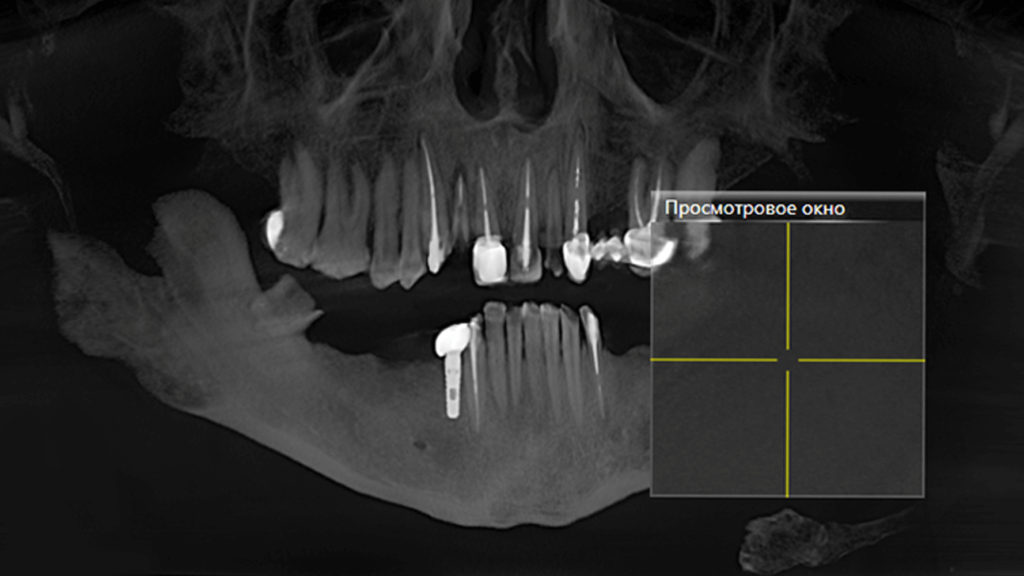

При осмотре пациента было обнаружено отсутствие восьми зубов: 5, 6, 7, 8 с правой и левой сторон на нижней челюсти. Нижние фронтальные зубы были поражены в результате патологического стирания вызванного массивной антагонистической конструкцией (металлокерамические коронки) на фронтальных зубах верхней челюсти. После 3D КТ-диагностики, осмотра и выслушав пожелания пациента, предложили следующий план лечения:

На первичной консультации врач провел осмотр полости рта, оценил КТ-снимки, составил план лечения и согласовал его с пациентом.